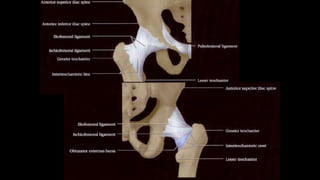

FEMUR

• + largo y resistente.

• Cuerpo y 2 extremidades

• Proximal: cabeza, cuello, trocánter

mayor y menor

• Distal: cóndilos

• La cabeza: medial, superior y

ligeramente anterior

• Limitado lateralmente por el trocánter mayor

• La línea intertrocanterea trayecto

inferomedial desde el trocánter mayor, pasa

por debajo del trocánter menor y se continua

con la línea pectínea de la cara posterior del

fémur producida por la inserción del

ligamento iliofemoral

ARTICULACION DE LA CADERA

COMPLEJO ARTICULAR Y LIGAMENTARIO

• Cápsula fibrosa rodea al acetabulo y se inserta en la

region intertrocantericza y carac posterior del cuello

femoral.

• Lig. iliofemoral anterior= extensión y rotación T-D.

• Lig. Pubofemoral= limita abducción

• Lig. Isquifemoral posterior= Limita extensión